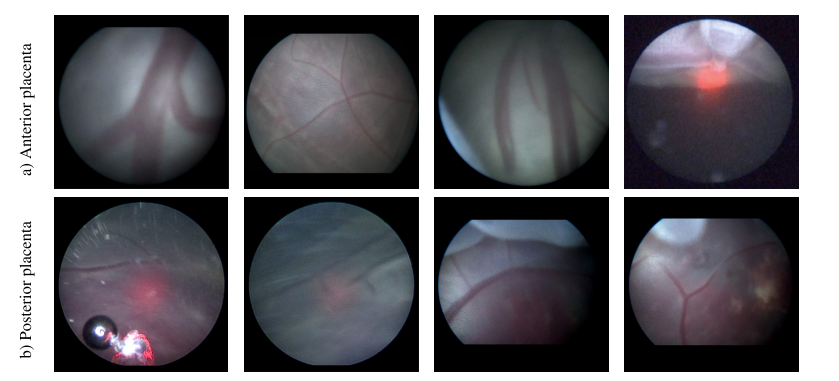

Fig. 13. Examples of video frames from two types of the placenta: (a) anterior, and (b) posterior placenta. We demonstrate that anterior placenta cases exhibit better visibility of placental vessels within the field of view compared to posterior cases, which impacts the segmentation performance of both types.

图 13. 来自两种类型胎盘的视频帧示例:(a)前置胎盘,(b)后置胎盘。我们展示了与后置胎盘相比,前置胎盘病例在视野内表现出更好的胎盘血管可见度,这对两种类型的分割性能产生了影响。